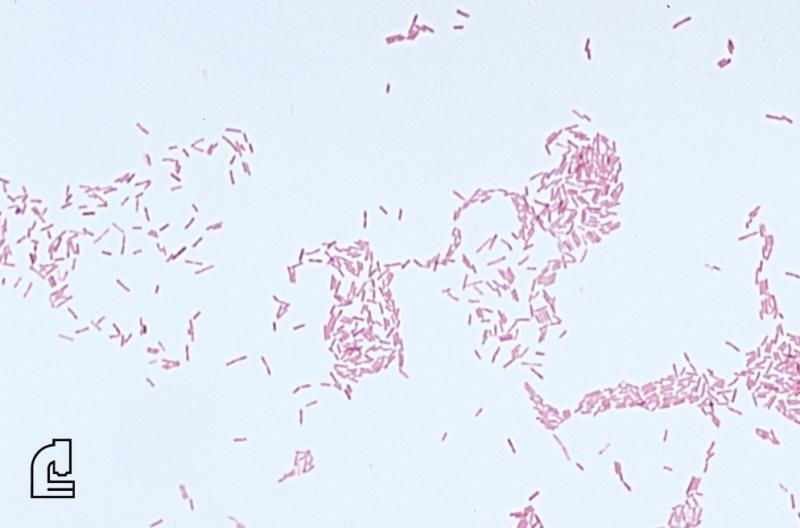

In addition to colour, which indicates whether the organism is Gram positive or Gram negative, the shape of the organism (such as rod-shaped) and the formation of groups of organisms is informative. For example, staphylococcus (staph) bacteria are found in clusters while streptococcus (strep) bacteria are found in chains.

The Gram stain involves applying a sample from an infected area or a sample of bacteria grown in culture onto a glass slide. The slide is then treated with a special stain and examined under a microscope by a trained laboratorian. The color and shape of the bacteria help classify which general types of bacteria are present.